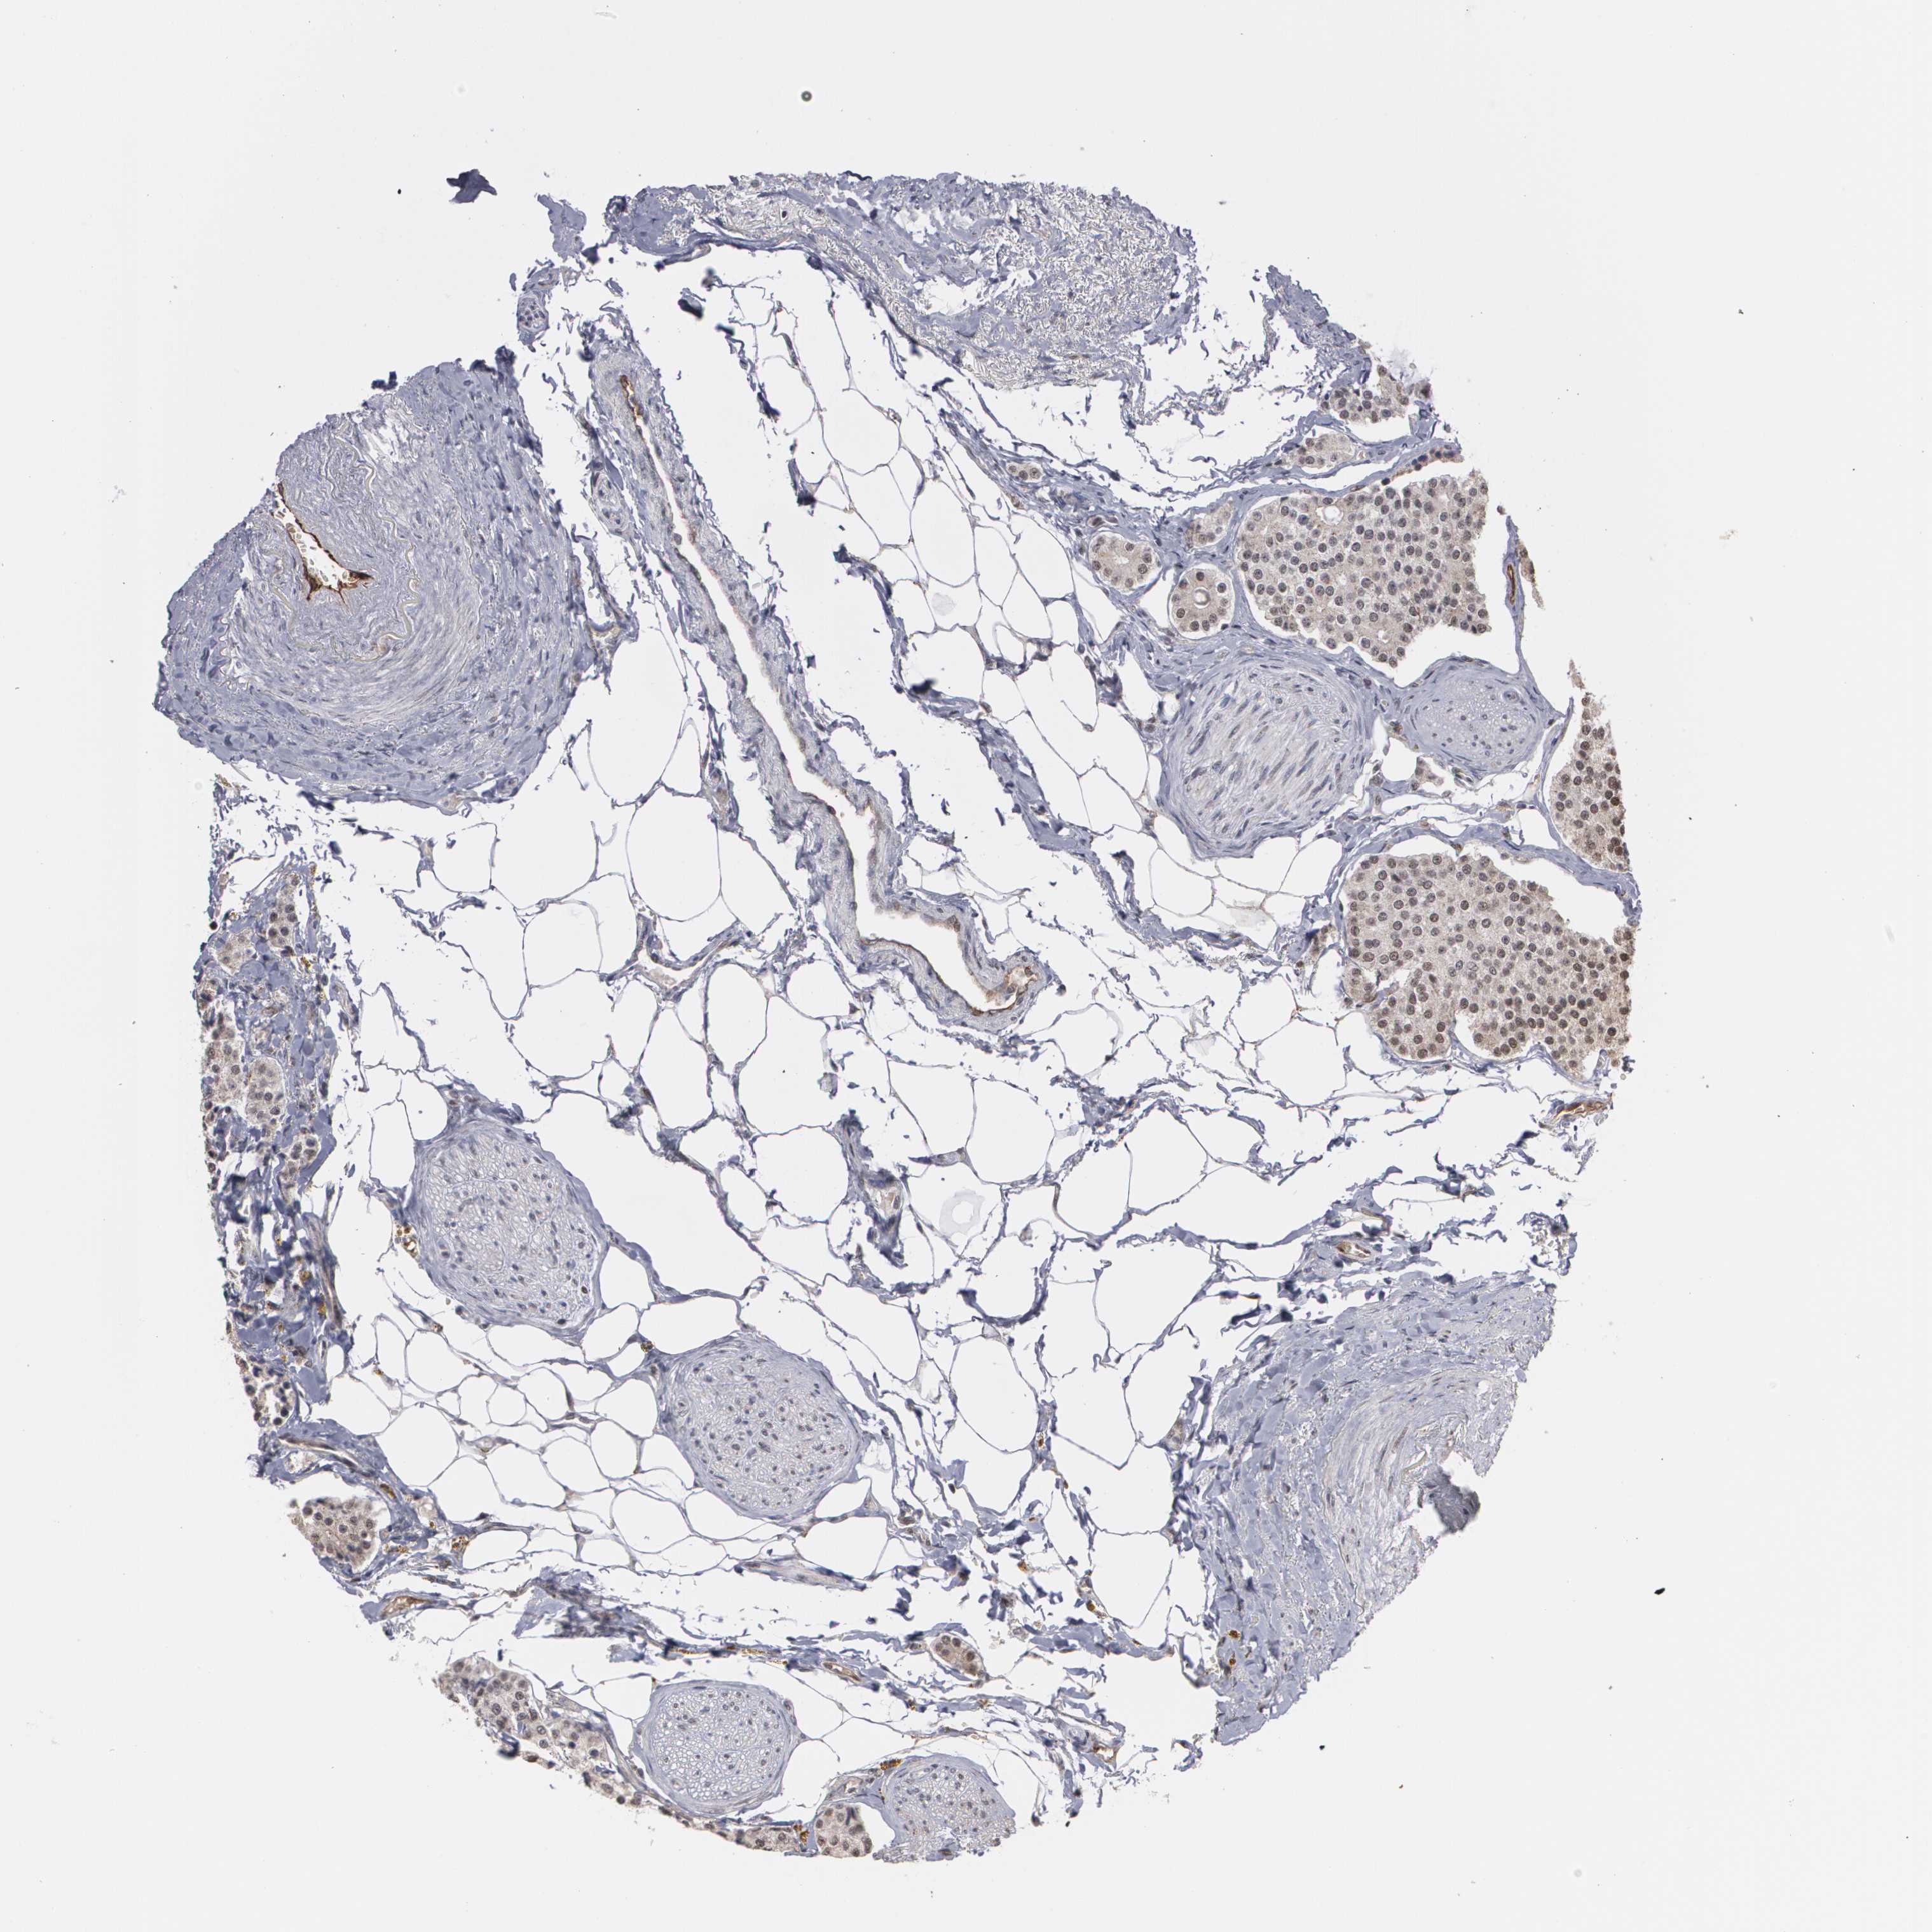

CARCINOID - Protein expressioni

A mouse-over function shows sample information and annotation data. Click on an image to view it in a full screen mode. Samples can be filtered based on level of antibody staining by selecting one or several of the following categories: high, medium, low and not detected. The assay and annotation is described here.

Antibody staining in the annotated cell types in the current human tissue is reported as not detected, low, medium, or high, based on conventional immunohistochemistry profiling in selected tissues. This score is based on the combination of the staining intensity and fraction of stained cells.

Each image is clickable and will lead to virtual microscopy that enables deeper exploration of all samples and also displays staining intensity scores, fraction scores and subcellular localization as well as patient and tissue information for each sample.

Antibody HPA001665

Carcinoid, malignant, NOS